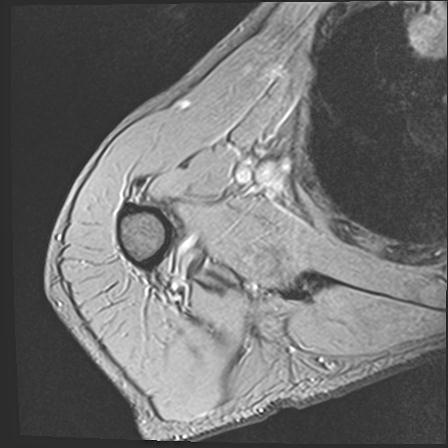

60058 3/9 11/4 右肩 2R+MRI 73歳男性 肩腱板損傷